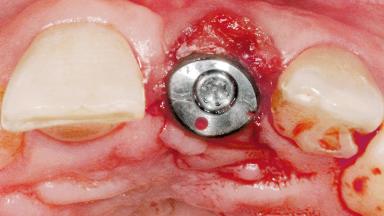

Late Flapless Placement of an Implant in a Maxillary Left Central Incisor Site

Type of Implants One-Piece

Attachment One-Piece

Abutment Type Standard

Prosthesis Type FDP

Retention Cemented, with prosthesis margin < 3mm submucosal Cemented, with prosthesis margin < 3mm submucosal

Provisional Implant-Supported Prosthesis Prosthodontic margin < 3 mm apical to mucosal margin Prosthodontic margin < 3 mm apical to mucosal margin